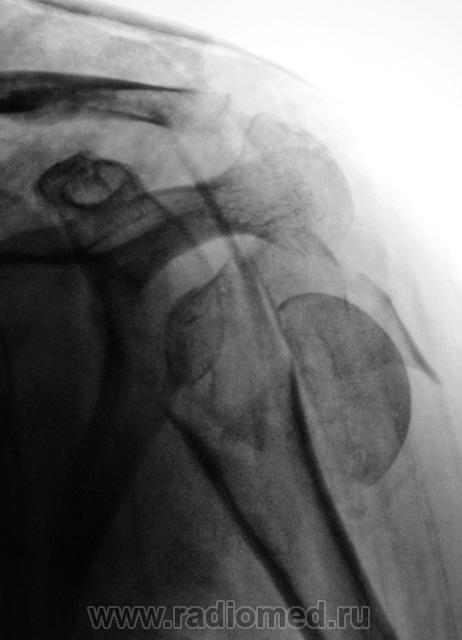

Пациент направлен в стационар - хирургическое отделение. Сегодня, пациент направлен для контрольной рентгенографии, после репозиции отломков и наложения повязки.

перелом головки плечевой кости, со смещением фрагментов кости каудально.

Плохо то, что пациент находится в обычном хирургическом отделении, а не госпитализирован в профильное травматологическое, и лечат пациента - хирурги.